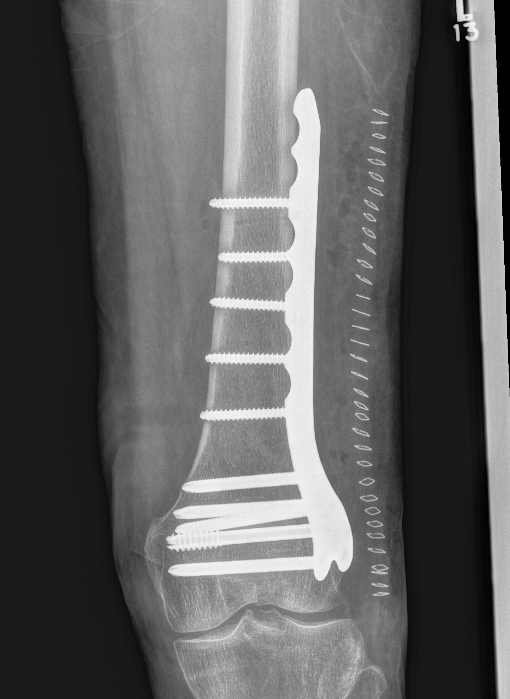

Lateral Plate

Surgical Technique

Apply plate distally

- length, valgus alignment, rotation restored

- ensure screws not in joint / above blumensaat's

- ensure screws not in PFJ (distal femur is trapezoidal)

MIPO plate technique

- percutaneously elevate muscle off femur with elevator

- insert appropriate length plate (4 bicortical screws above)

- second proximal incision

- obtain indirect reduction

- attach plate with screws

Tips

- longer plate better

- titanium plate better

- reduce rigidity better - proximal screws away from fracture

- cortical non locking screws in proximal plate